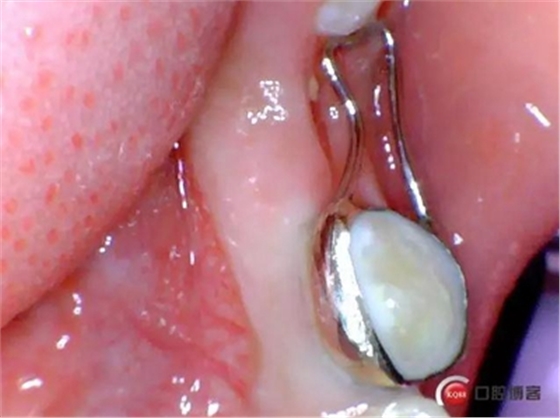

一周后患者復(fù)診,拔牙創(chuàng)恢復(fù)良,制作*74口內(nèi)帶環(huán)并焊接,反復(fù)試戴合適后藻酸鹽取上下頜模型并發(fā)加工廠做保持器。電話預(yù)約復(fù)診時(shí)間。

保持器回來(lái)后電話預(yù)約患者復(fù)診,反復(fù)試戴合適后消毒隔濕干燥,常規(guī)富士Ⅸ粘結(jié)保持器,調(diào)合,拋光,囑患者注意口腔衛(wèi)生并預(yù)約半年復(fù)查一次。